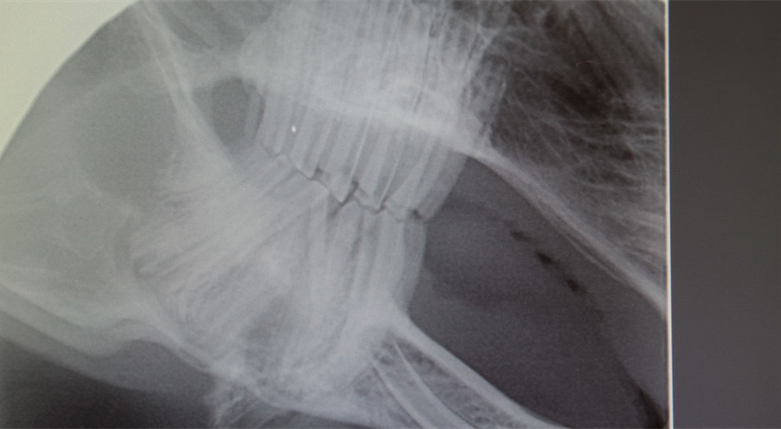

De har en lang liste over tjenester som utføres og dyreklinikken kan sammenlignes med et sykehus for mennesker. Her utføres alt fra helsekontroller, vaksiner, indremedisinske utredninger, hjerteutredninger, tannbehandling, ortopediske operasjoner, kikkhullskirurgi til nedfrysing/oppbevaring av sæd for avl. I tillegg er også Dyreklinikken Bergen Vest ansvarlige veterinærer for Akvariet i Bergen og geitene på Fløyen.